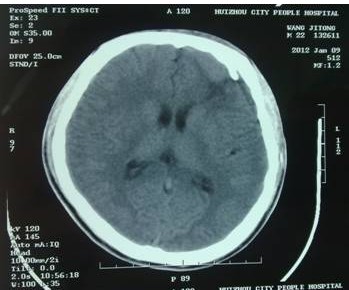

2011年12月,一位患者幾經(jīng)輾轉(zhuǎn)慕名來到我院,求助于余永強(qiáng)主任。患者為年輕男性,是一名汽修廠工人,由于工作時(shí)輪胎爆炸導(dǎo)致頭部受傷,外院CT提示額骨左側(cè)粉碎性骨折并左額葉腦內(nèi)血腫,血腫量約40ml,已經(jīng)達(dá)到了開顱手術(shù)指征(圖1)。當(dāng)?shù)蒯t(yī)院擬予開顱手術(shù)。但是家屬考慮到開顱手術(shù)的風(fēng)險(xiǎn),同時(shí),由于額骨粉碎性骨折,如果接受傳統(tǒng)開顱血腫清除手術(shù),除了手術(shù)對腦組織的損傷外,還面臨一個(gè)問題是局部顱骨無法保留,需要再行顱骨修補(bǔ)手術(shù),勢必增加患者經(jīng)濟(jì)負(fù)擔(dān),也會在頭部留下不小的手術(shù)疤痕。這對于一個(gè)二十來歲的年輕人來說也是難以接受的。

圖1:術(shù)前CT掃描,額骨左側(cè)粉碎性骨折,左額葉腦內(nèi)血腫約40ml,手術(shù)指征明確。